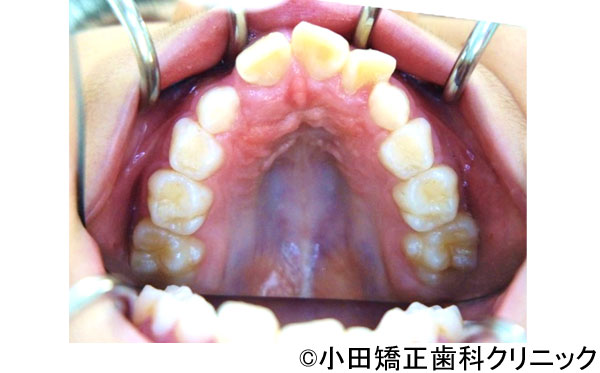

- 治療前

- 治療後

- 呼吸から治して厳しいでこぼこ状態ではあるが、歯を抜くことなくしかも突出のない知的な口元に改善する治療

- 患者様

- 9歳

- 費用

- 1,000,000円(税込)(永久歯治療を含む)

- 期間

- 早期治療2年+永久歯治療1年

患者様の症状

-

厳しい上下歯列のでこぼこ不十分な鼻呼吸のため口呼吸が必要となり、舌、唇などの筋肉の良くない動き、つまり舌が、本来、飲み込むために上あごに引っ付くのではなく、下に下がり、口が開くことで頬が締まって上歯列は狭くなります。また下に下がった下の圧力で下歯列も内側に倒れて狭い舌歯列となります。

鼻呼吸不十分による口呼吸がもたらす締まりにかけるやや突出した口元、不適切な姿勢、免疫機構の不善によりもたらされる過大な感染症のリスク -

治療法

上歯列に固定式の拡大装置により左右の上あごの接合部を拡げて鼻呼吸に改善する。舌が収まる空間を得るために下歯列にも特殊な拡大装置により歯を支える骨の付け根からしっかりと広げる。

治療結果

美しい口元、顔立ち、健康的な呼吸をもたらし、鼻呼吸を導く徹底した従来より効果の大きい広げる装置により、厳しいでこぼこ状態を歯を抜くことなく、しかも突出の全くないきれいな口元に改善しました。